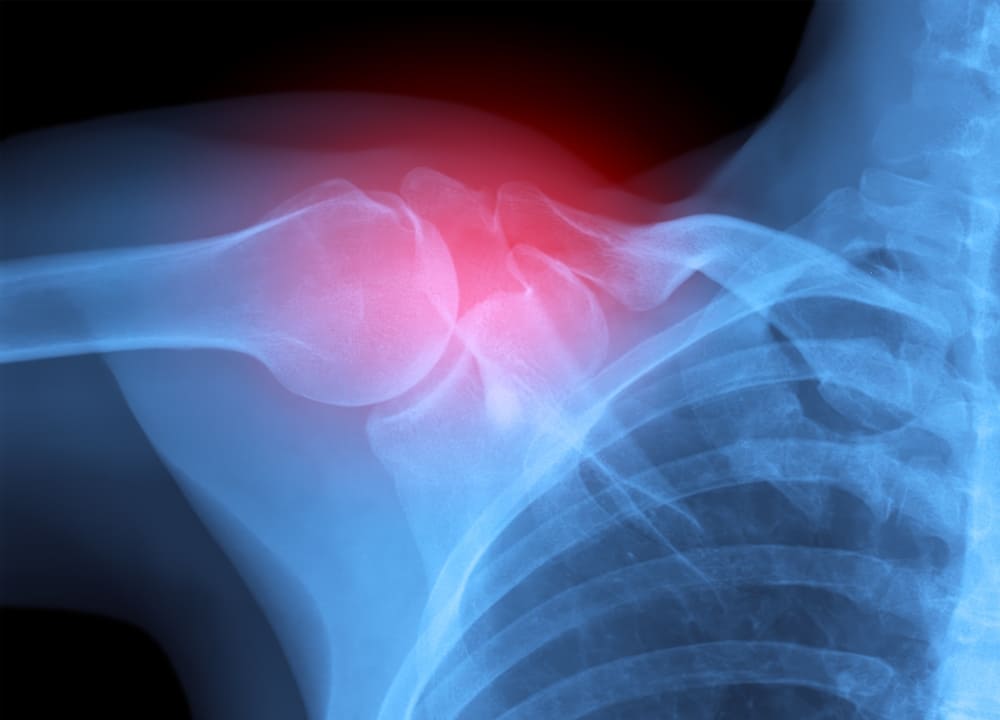

Посттравматический артроз

Посттравматический артроз — это хронический патологический процесс дегенеративного характера, для которого типично медленное, но неуклонное разрушение хряща. Как и следует из названия патологического состояния, оно развивается после перенесенной травмы или иного повреждения. Обычно на фоне внутрисуставных переломов, тяжелых вывихов, но не только. Порой причиной становятся расстройства и нарушения со стороны мягких тканей. Например, связочного аппарата конечности. В каждом конкретном случае требуется тщательная диагностика. Определение исходной причины нарушения, степени выраженности патологического процесса и прочих индивидуальных факторов.

Диагностика посттравматического артроза

- рентгенография;